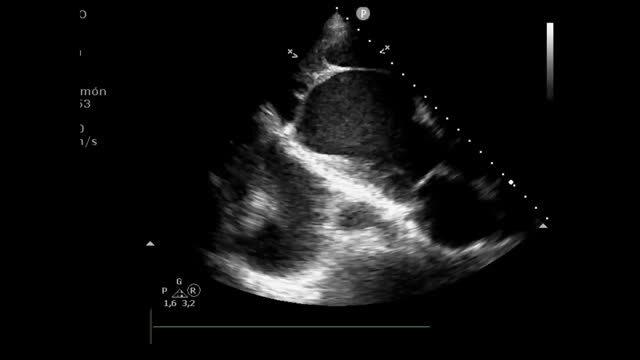

Presentamos el caso de una paciente de 61años con infarto de miocardio evolucionado hace un mes, que presentó complicaciones mecánicas postinfarto. La ecocardiografía evidenció un pseudoaneurisma apical de gran tamaño (fig. 1 y fig. 3: fecha azul) (Vídeo Anexo 1), con cuello de 2,93cm (fig. 1 y fig. 2: flecha amarilla) y paso de ecocontraste libre a su través (fig. 2: fecha roja), con la luz parcialmente trombosada (fig. 1 y fig. 3: fecha blanca). Se observó también un ventrículo izquierdo severamente dilatado y disfunción sistólica global muy severa (fig. 1) (FEVI 11%, IVT TSVI 7cm). A las 48horas de ingreso la paciente desarrolló shock cardiogénico SCAIC-D, que requirió soporte mecánico con ECMOV-A y balón de contrapulsación intraaórtico, logrando una notable mejoría de la perfusión orgánica. Tras coordinación con el hospital de referencia, fue trasplantada cardiaca código0, con una recuperación favorable. Este caso destaca la importancia del diagnóstico ecocardiográfico y el manejo con soporte mecánico en situaciones críticas de shock cardiogénico.